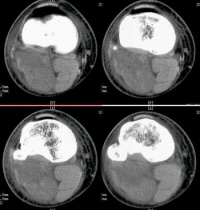

咽淋巴环病变通常占恶性淋巴瘤的10%~15%,96%为弥漫性原淋巴细胞及组织细胞型淋巴瘤,发生部位最多在软腭、扁桃体,其次为鼻腔及鼻窦,临床有吞咽困难、鼻塞、鼻衄及颌下淋巴结大。NHL较HD更有结外侵犯倾向,尤其是弥漫性组织细胞性淋巴瘤。结外累及以胃肠道、骨髓及中枢神经系统为多。NHL累及肠胃道部位以小肠为多,其中半数以上为回肠,其次为胃,结肠很少受累。临床表现有腹痛、腹泻和腹块,症状可类似消化性溃疡、肠结核或脂肪泻等。个别因肠梗阻或大量出血经施行手术而确诊。肝经活组织证实约1/4~1/ 2受累,脾肿大仅见于较后期病例。胸部以肺门及纵隔受累最多,半数有肺部浸润或(和)胸腔积液。尸解中近1/3可有心包及心脏受侵。中枢神经系统病变多在疾病进展期,约有10%,以累及脑膜及脊髓为主。骨髓累及者约1/3~2/3,与类型有关,骨骼虽还以胸椎及腰椎最常见,股骨、肋骨、骨盆及头颅骨次之。弥漫性大细胞或组织细胞型可原发于骨骼,患者年龄较轻,多在长骨,主要是溶骨性。皮肤表现较HD为常见,多为特异性损害,如肿块、皮下结节、浸润性斑块、溃疡等。肾脏损害尸解有33.5%,但临床表现仅23%,主要为肾肿大、高血压及尿素氮贮留。近年来淋巴瘤合并肾病综合征已屡有报道,随淋巴瘤缓解而好转。

恶性淋巴瘤约 2% 左右可发生于肺部,表现为肺野内边界清楚的圆形或分叶状阴影,患者自觉症状很少。有的患者可侵犯肺门或纵隔淋巴结,一般很少有上腔静脉压迫征或纵隔肌麻痹,治疗预后也较好。由纵隔侵犯肺部的恶性淋巴瘤多靠近肺门,常常连成一片,可为单侧或双侧性,并常伴有气管旁淋巴结肿大,也易引起压迫症状,其预后不如原发于肺的病例。

小肠恶性淋巴瘤在手术时 50% 以上以有肠系膜淋巴结受侵,如小肠肿块较大,有溃疡、多发,并侵犯淋巴结则预后不佳。恶性淋巴瘤从肠黏膜下层的淋巴滤泡开始,向内侵及黏膜层,向外达肌层。由于黏膜与黏膜肌层有瘤组织侵润,正常黏膜皱襞消失变平坦。肠壁增厚、僵硬,甚至蠕动消失。